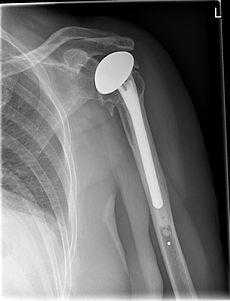

Полная замена илитотальное эндопротезирование плечевого сустава. Стержень плечевого протеза может закрепляться на цементе или бесцементно. © Gelenk-Klinik

Полная замена или тотальное эндопртезирование плечевого сустава. Стержень плечевого протеза может закрепляться на цементе или бесцементно.

Полная замена плечевого сустава

Полная замена плечевого сустава или тотальное эндопротезирование плечевого сустава. Плечевой компонент зафиксирован внутри плечевой кости. Гленоидный компонент замещает суставную впадину. © Wikipedia

При полной замене плечевого сустава заменяются оба компонента сустава: плечевая головка и суставная впадина. Это самый распространенный метод замены плечевого сустава. При износе обеих поверхностей сустава, как плечевой головки так и суставной впадины, необходим полный эндопротез. При таком методе замены удаляется сегмент плечевой головки, наиболее близкий к суставу. Затем внутренняя часть (пространство костного мозга) плечевой кости подготавливается для внедрения ножки протеза.

Ножка протеза имплантируется вовнутрь кости. Одним из наиболее тяжелых осложнений при полной замене плечевого сустава является ослабление гленоидного компонента. Это ведет к возникновению боли и ограничению подвижности.

Поэтому тщательная диагностика, оптимальный подбор размера и подгонка компонентов протеза является необходимым аспектом плечевой хирургии. Специалисты по плечевым суставам должны также детально оценить риск таких осложнений, как остеопороз (снижение плотности кости).